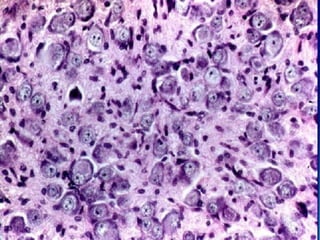

CASO CLINICO

(para primer año)

• MASCULINO DE 32 AÑOS QUE

PRESENTA DESDE HACE 5 MESES

CAMBIOS EN EL ESTADO MENTAL,

EPILEPSIA, CEFALEA Y MALESTAR

GENERAL.

• SE SOMETE AL PACIENTE A

RESONANCIA MAGNETICA

ENCONTRANDO LO SIGUIENTE:

• AL OBSERVAR EL TUMOR EN LA

IMAGEN SE DECIDE SOMETER AL

PACIENTE A UNA BIOPSIA DEL TUMOR

• SE ENCUENTRA LO SIGUIENTE

DIAGNOSTICO:

OLIGODENDROGLIOMA

PATOLOGICO

NORMAL